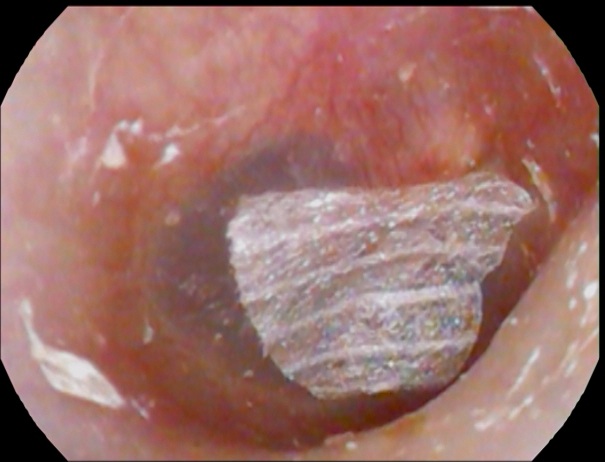

これは 「3日前から耳が痛くて聞こえが悪い」とのことで当院受診された患者の耳

の写真です。

外耳道に、膿&カビの塊が充満しています。

原因は耳掃除のし過ぎで耳の穴を傷つけ、そこにカビが付着し増殖という患者さんが多いです。傷がついた後で 長時間イヤホンを付けて生活している場合はハイリスクとなります。

治療としては、まずは耳鼻科を受診し耳の中を綺麗にすることです。抗真菌薬投与、さらに耳を触らないことが大切です。

実は、今回受診された患者さん 7年前にも外耳道真菌の診断での治療歴がございます↓

カビは治療でいったん消えたあとでも、繰り返しやすいという特徴があります。

耳

は診てみないと分かりません。耳症状のある方は、耳鼻咽喉科の受診をおススメいたします